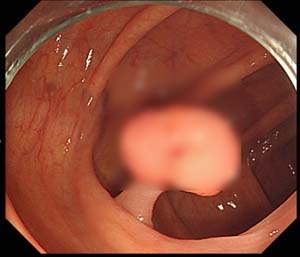

선종성 용종은 대장에 생기는 혹으로 대다수 의 대장암은 원인에 문제될 것 없이 선종성 용종이라고 부르는 암의 전 스탭를 거쳐 암으로 발전하게 되겠습니다. 선종성 용종은 증상이 없는 50세 이상의 성인이 대장 내시경을 하게 되었다면 약 30% 정도에서 발견되겠습니다.

선종성 용종이 얼마나 암으로 발달할 위험이 있는지는 용종의 크기와 현미경적 조직 생각에 따라 격차가 있어요. 범위가 1cm보다 작은 경우는 암세포가 들어 있을 확률이 1% 정도이지만 2cm보다 크면 암세포가 들어 있을 확률이 약 35~50%나 되겠습니다. 또한 조직검사에서 융모성 성분을 충분히 내포하고 있을 경우 암으로 추진할 가능성이 높아지고요.